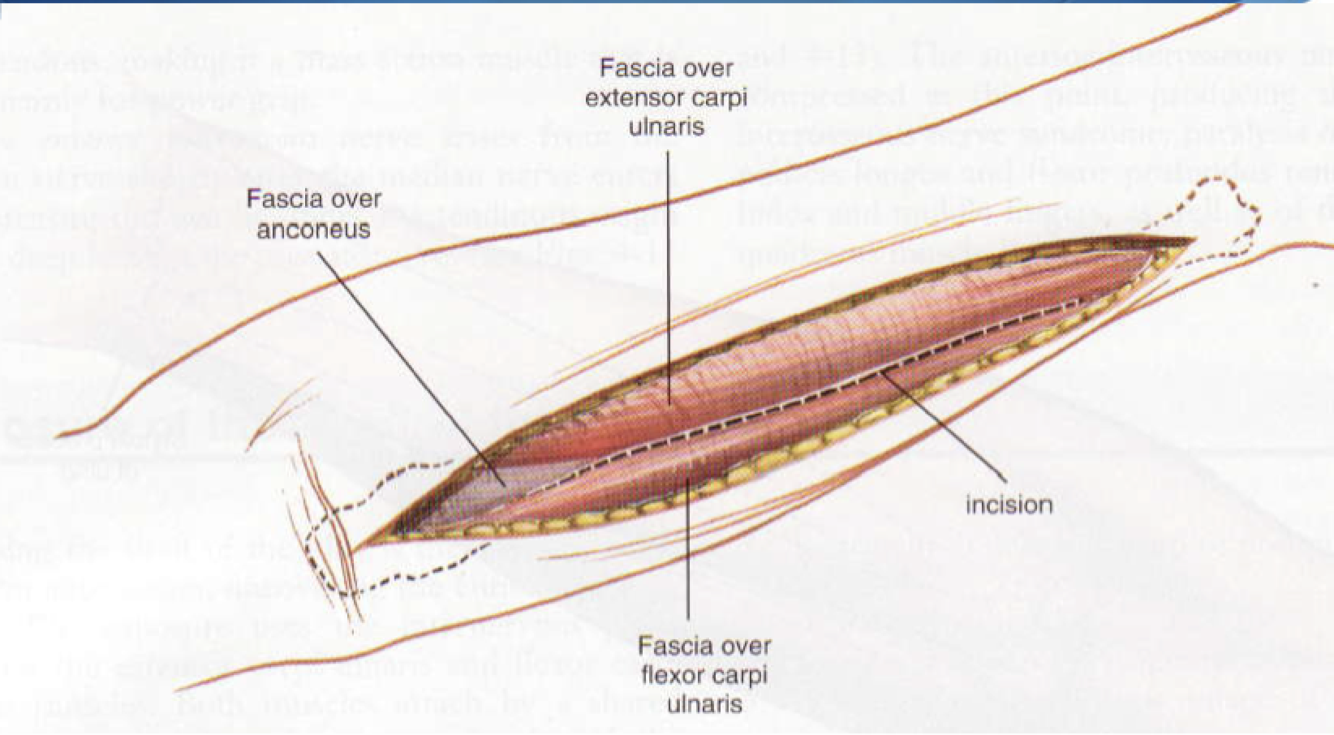

Approach to Ulnar Shaft

Interval: ECU (PIN), FCU (Ulnar N.)

Approach: Dissect onto subcutaneous boarder of ulna. Lift ECU and FCU subperiosteally to expose.

Dangers: Ulnar N (under FCU, ontop of FDP), Dorsal cutaneous branch of ulna distally, Ulnar A (runs with Ulnar N, radial to ulnar N)